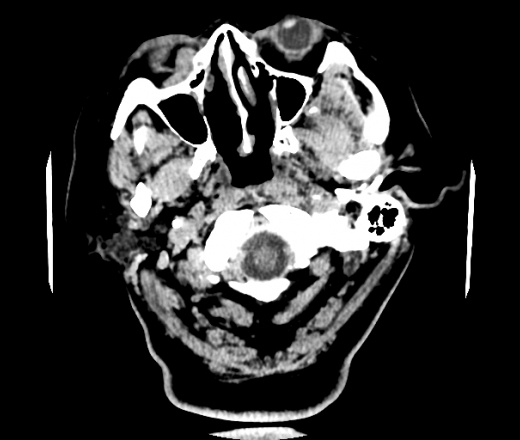

Женщина 48 лет, поступила с подозрением не ОНМК. На КТ -данных за ОНМК не обнаружено, но в правой орбите ретробульбарно мягкотканное образование +45HU, признаков деструкции и ремоделирования костных структур орбиты не наблюдается, медиальная и нижняя прямая мышца отчетливо не дифференцируются, зрительный нерв тесно прилежит к данному образованию. После КУ гомогенное накопление КВ и повышение плотности до +65HU. Экзофтальм. Жалобы на снижение зрения. Год назад делала МРТ ГМ, на снимке патологии орбит не увидел. Идиопатическая псевдоопухоль орбиты?

В мягких тканях носогубного треугольника справа тоже образование.

Натив

Контраст